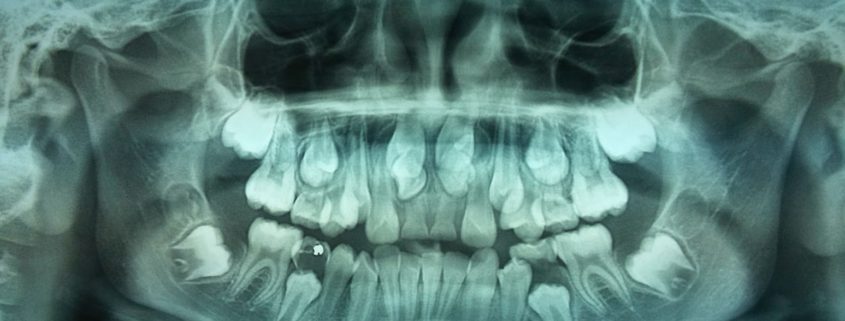

Vantaggi della Radiografia Panoramica delle Arcate Dentarie

I vantaggi di strumenti diagnostici quali la panoramica digitale e la tac dentalscan sono indiscutibili quando si vuole appurare lo stato delle arcate dentarie e verificare la fattibilità dell’intervento di implantologia dentaria o di qualsiasi cura odontoiatrica.